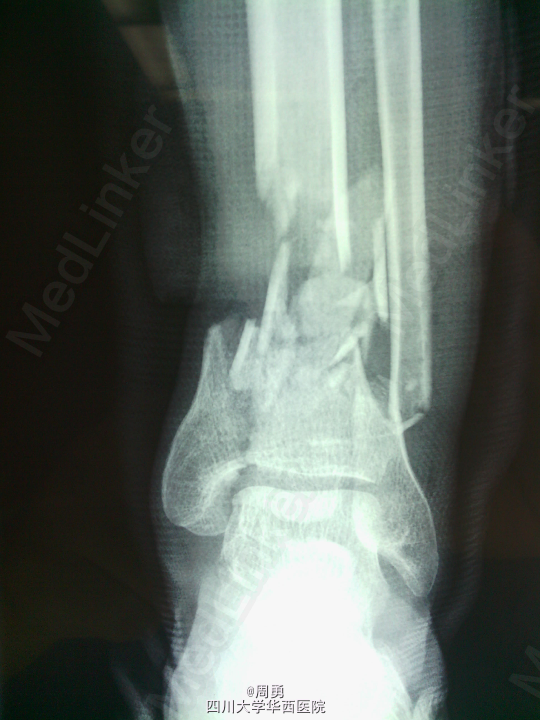

闭合穿针复位腓骨在开放性骨折中应用和意义

某些腓骨骨折常无需处理,但在开放性骨折一期处理创面同时,为了达到恢复肢体长度、条件允许情况下最大可能复位骨折、简化二期手术目的,某些时候复位腓骨并闭合穿克氏针对骨折复位和固定会有一定帮助,选几年前2个博士住院总期间X片示意,欢迎大家交流。